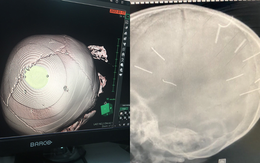

Vụ bé 3 tuổi bị nhân tình của mẹ đóng đinh ở đầu: Đáp ứng điều trị kém, tiên lượng dè dặt

16/02/2022 13:50

Đại diện Bệnh viện Xanh Pôn cho hay, theo báo cáo của bác sĩ điều trị, hiện tại bệnh nhi 3 tuổi bị người tình của mẹ đóng 9 đinh vào đầu đáp ứng điều trị kém, tiên lượng dè dặt.

Lời cầu cứu không được hồi đáp của bé 3 tuổi bị đọa đày và giọt nước mắt ân hận của bà nội

21/01/2022 11:07

Bà nội em bé 3 tuổi bị ghim đinh vào đầu bật khóc nhớ lại những lần níu giữ cháu lại, xin mẹ cháu ở lại hàn gắn gia đình nhưng bất thành.

NÓNG: Tạm giữ hình sự mẹ bé gái 3 tuổi ở Hà Nội và nhân tình để điều tra hành vi bạo hành

19/01/2022 13:49

Lãnh đạo UBND huyện Thạch Thất thông tin công an đã tạm giữ người mẹ và người tình của người phụ nữ này để làm rõ việc bé gái 3 tuổi nguy kịch, có nhiều đinh găm vào đầu.

Vụ bé gái nghi có đinh ở đầu: Người mẹ 10 năm yêu thương con bỗng 'thay tính đổi nết'?

19/01/2022 09:33

Theo lời kể của chị Huyền Anh thì mẹ bé A. có khoảng 10 năm hết mực yêu thương các con nhưng kể từ đầu năm ngoái bất ngờ bỏ các con trốn đi biệt tích.